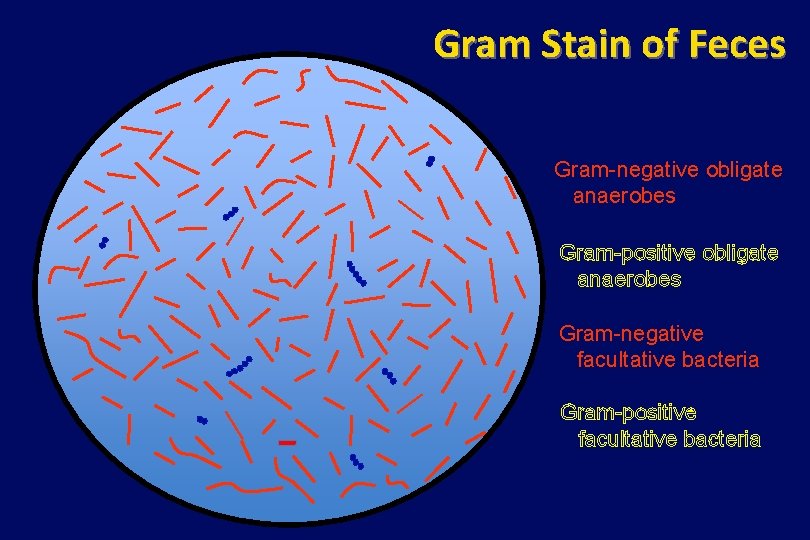

Gram Stain of Feces Gram-negative obligate anaerobes Gram-positive obligate anaerobes Gram-negative facultative bacteria Gram-positive facultative bacteria